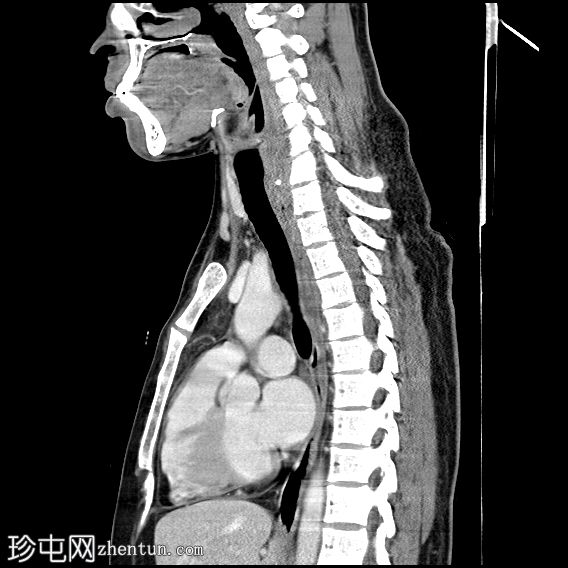

矢状位增强扫描(门静脉期)

颈段食管内可见一线状水平方向的高密度异物。

颈段和上胸段食管可见长段环周强化壁增厚,符合异物嵌顿引起的反应性水肿改变。

可见食管壁撕裂,可能与异物的方向有关。此外,可见多个食管周围气腔,提示可能存在食管穿孔。

未见纵隔积气、食管周围脓肿或明显穿孔的证据。